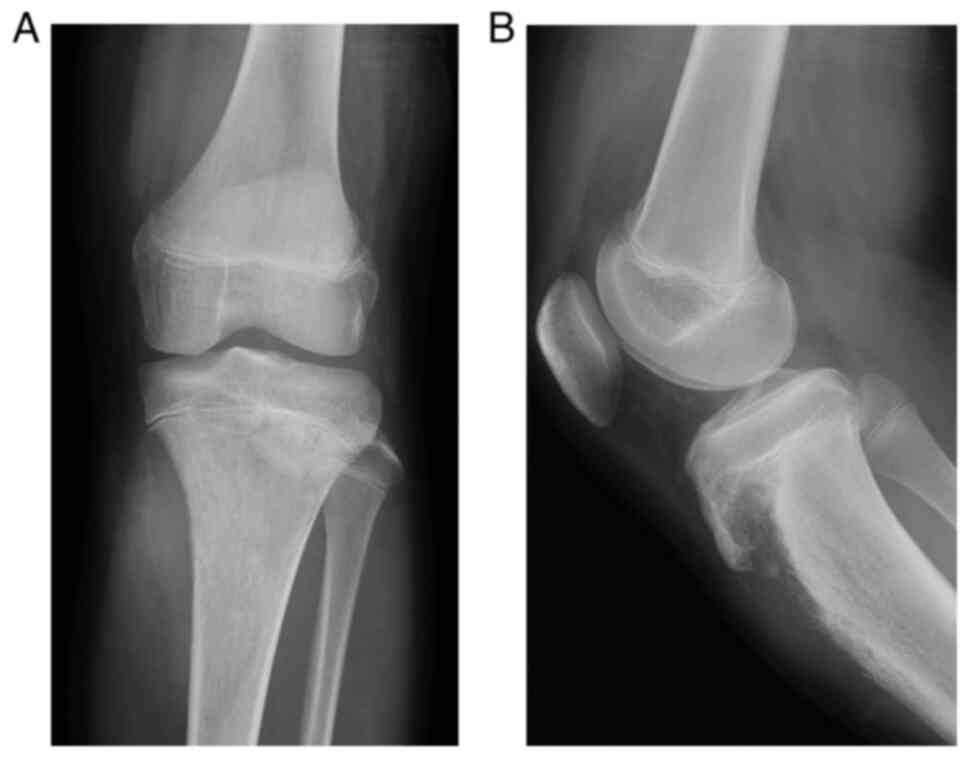

Soft Tissue Tumor - CT Guided Biopsy, em>BCOR‑CCNB3 sarcoma arising in the proximal tibia: A

em>BCOR‑CCNB3 sarcoma arising in the proximal tibia: A洋書 [A12364013]Interest Rate Modeling. Volume 1: Foundations and Vanilla Models